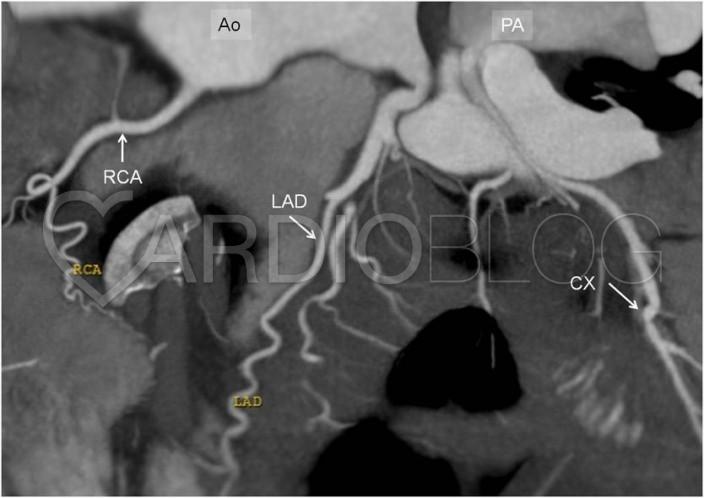

Az elvégzett coronaria CT angiographia tanulsága szerint a coronariák ectaticusak, kanyargós lefutásúak. A kanyarodó multiplanaris rekonstrukciókon jól ábrázolódik a jobb artéria pulmonalisból eredő körbefutó ág (CX). Az artéria pulmonalisban uralkodó nyomás jóval alacsonyabb a coronaria rendszer nyomásánál, így a kontrasztdús vér a CX-ből az arteria pulmonalis irányába áramlik, így a magasabb nyomású coronaria rendszer és az arteria pulmonalis között bal-jobb shunt alakul ki, mely „coronary steal phenomenon” kialakulásához vezet.